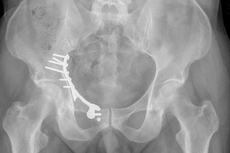

Beckenfrakturen

Beckenfrakturen und Frakturen der Hüftgelenkspfanne (Azetabulum) sind komplizierte, teilweise sogar lebensbedrohende Verletzungen. Schwere, instabile Beckenbrüche treten häufig in Verbindung mit Hochenergieverletzungen wie einem Polytrauma auf. Gefäß- und Nervenverletzungen sind in deren Folge nicht selten und können zu einem massiven Blutverlust führen. Die Erstversorgung hängt von der Schwere der Fraktur und der Begleitverletzungen ab. Bei schweren Verletzungen ist zunächst eine Stabilisierung mit einer Beckenzwinge oder einem Fixateur externe notwendig, um andere Verletzungsfolgen primär zu behandeln.

Zur weiterführenden Diagnostik einer Beckenverletzung steht uns modernste radiologische Bildgebung mit 3D-Rekonstruktion zur Verfügung. Auch intraoperativ ist eine 3D-Bildgebung bei laufender Operation möglich. Zur Therapie von vorderen und hinteren Beckenring-Frakturen favorisieren wir Platten-Osteosynthesen offener Reposition, aber auch minimal-invasive Therapieoptionen und transkutane Verschraubungen.

Frakturen der Hüftgelenkspfanne

Frakturen der Hüftgelenkspfanne (Azetabulumfrakturen) sind häufig komplizierte Frakturen. Die Schwierigkeit der Versorgung liegt in der exakten Wiederherstellung der konkaven Gelenkfläche. Auch bei optimaler Versorgung kann sich aus einer Azetabulumfraktur ein frühzeitiger Hüftgelenksverschleiß entwickeln.

Die Therapie-Entscheidung berücksichtigt die individuelle Situation des Verletzten wie Lebensalter, Knochenqualität, körperliche Aktivität u.v.m. und bedarf hoher operativer Erfahrungen. Neben den oben genannten Verfahren kommt auch die sofortige endoprothetische Versorgung mit speziellen Stützschalen in Betracht. Sie gewährleistet gerade bei älteren Menschen eine frühzeitige Mobilisation.